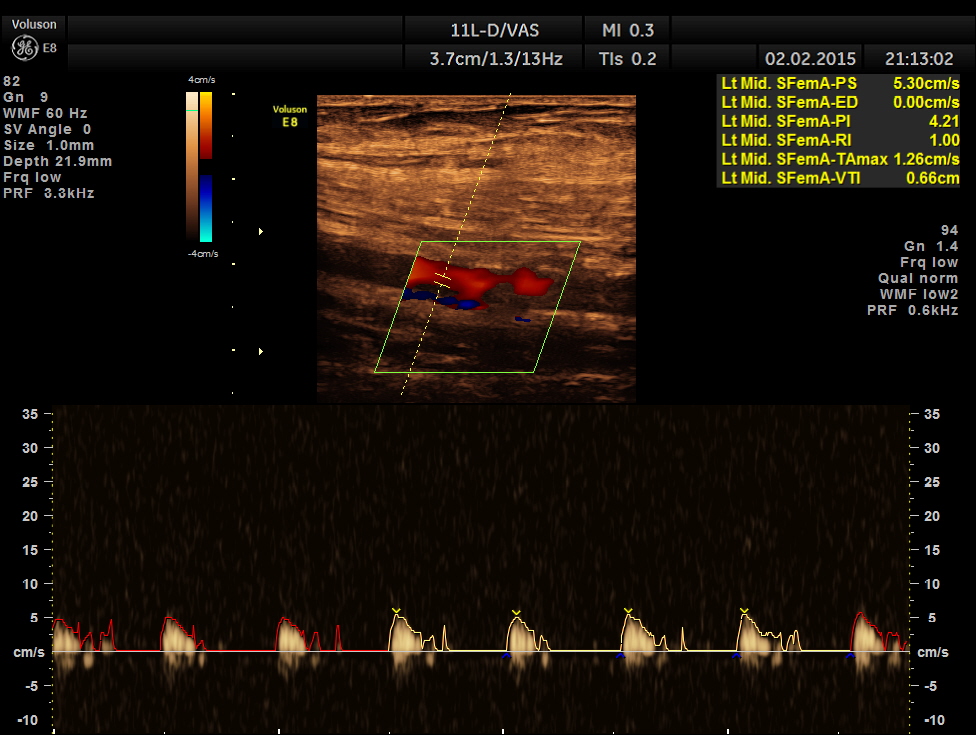

left proximal superficial femoral artery shows reduced peak systolic velocity

the following pictures show progressive fall of peak systolic velocity with no flow made out in the distal superficial femoral artery.